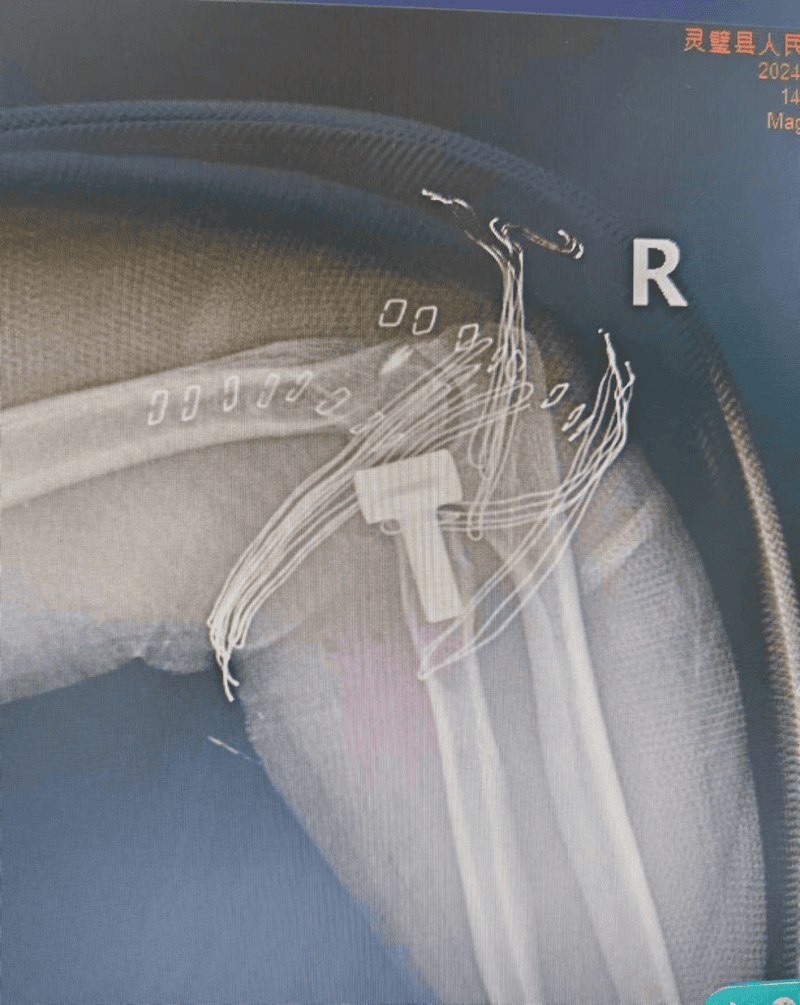

图为术后复查